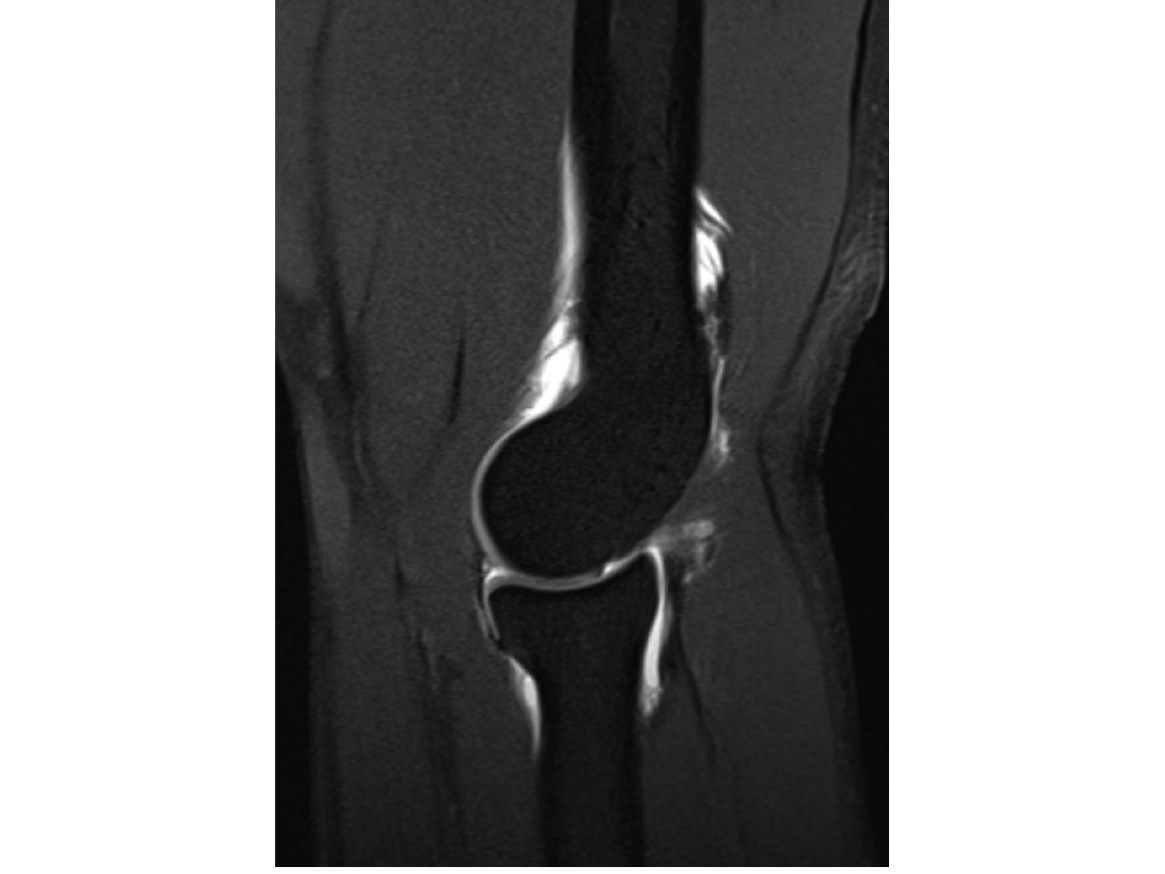

Sagittal T1 Fat Saturated image demonstrating an elbow arthrogram, which was obtained after administration of contrast via ultrasound.